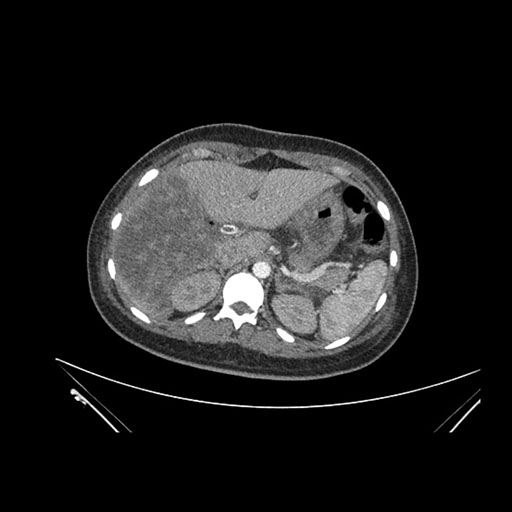

Axial Venous